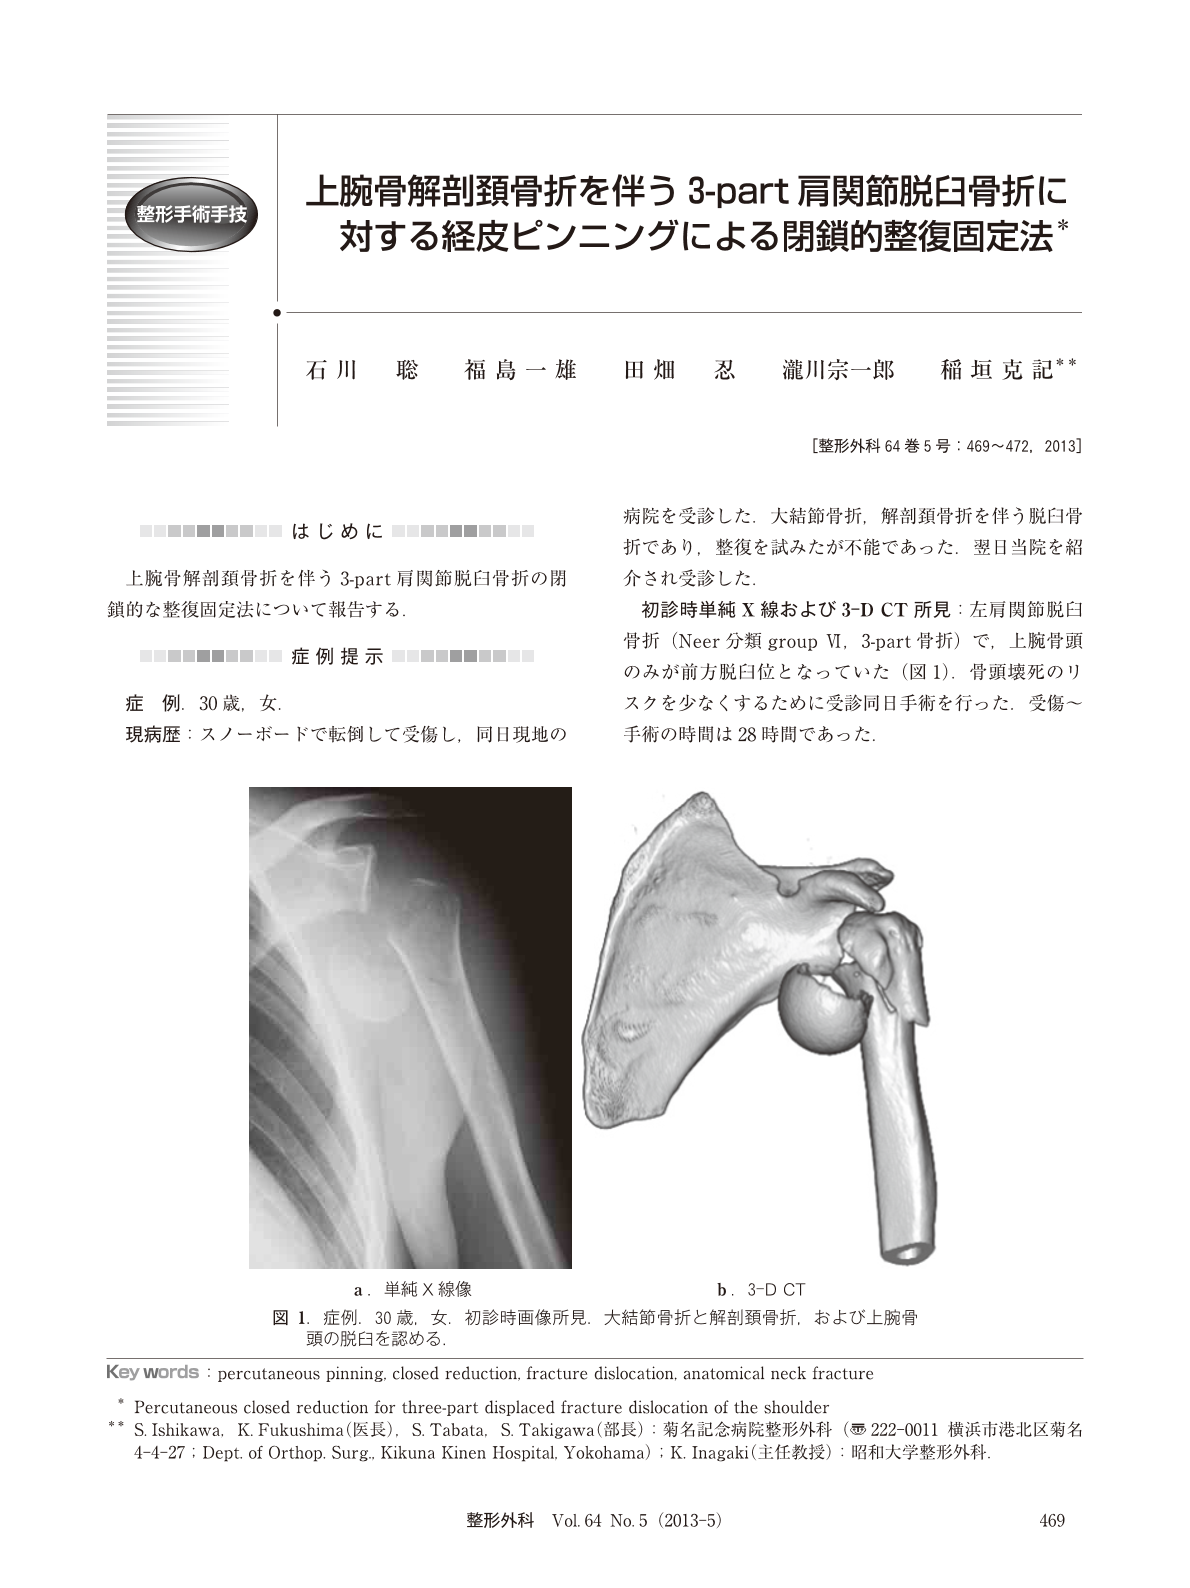

上腕骨解剖頸骨折を伴う3 Part肩関節脱臼骨折に対する経皮ピンニングによる閉鎖的整復固定法 臨床雑誌整形外科 64巻5号 医書 Jp

陳美鳳跌倒致 脫臼型骨折 醫 年長病人得留意併發症 康健雜誌